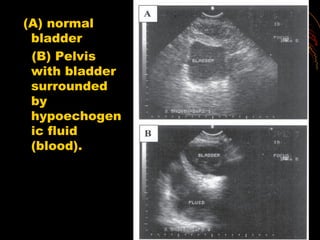

(A) normal

bladder

(B) Pelvis

with bladder

surrounded

by

hypoechogen

ic fluid

(blood).

(A) normal bladder (B) Pelvis withbladder surrounded by hypoechogen ic fluid (blood).